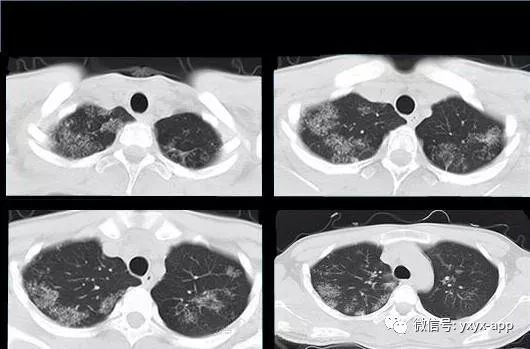

评论:两肺斑片状磨玻璃影,与周围组织分界清楚,呈“地图样”表现,部分病变延伸至胸膜下,部分小叶间隔增厚,气管居中,肺门及纵膈未见肿大淋巴结影,未见胸腔积液。患者青年男性,临床症状轻微影像表现严重,抗炎治疗无效。考虑肺泡蛋白沉积症

1、两肺较淡的斑片状磨玻璃影,不呈叶段分布,病变可延伸至胸膜下,其中磨玻璃影中可见小结节影,磨玻璃影与正常肺组织分界清楚,形成“地图样”改变,这种地图样分布的原因,可能是由于这种斑片影以肺小叶为病变单位,小叶间隔在一定程度上限制了病变的蔓延;

2、由于小叶间隔和小叶内间隔的增厚形成网格状阴影改变,弥漫的磨玻璃影及其内部的网格小叶间隔增厚形成了“铺路石样”改变;

④ 肺出血:各种原因引起的肺出血,与本病影像表现相似,亦可见磨玻璃影,但无小叶间隔增厚及铺路石征等表现,出血性疾病短期内随访病变有明显吸收。